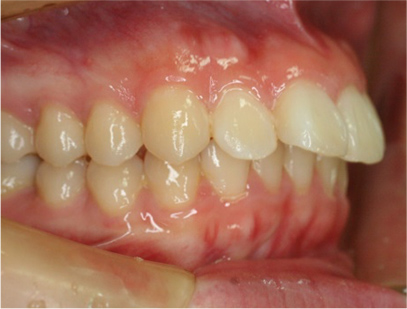

• 左側

• 右側